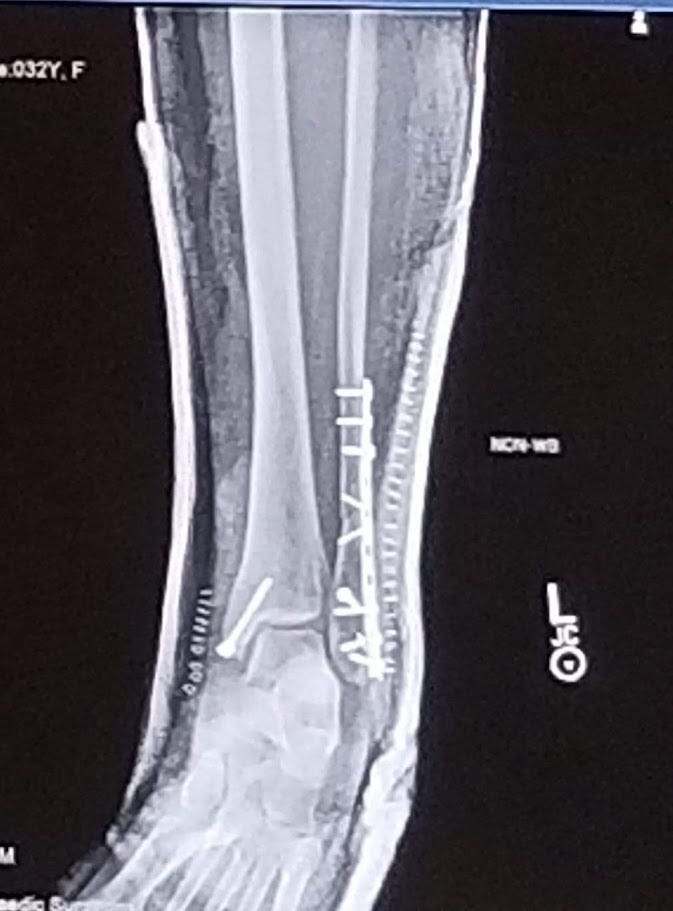

She has two steel rods in her leg to this day after such an egregious break and facture with a nice Canada tattoo to commemorate the occasion with socialized medicine. The hardest part of the whole ordeal wasn’t a long wait time or hearing the Canadians ask what we were “aboot” there. It was dealing with the insurance company and the uncertainty that it brought. Most of my stress after the initiate checking in that she was going to be OK was “what are we going to have to pay for this” and “can we even afford to get that operation if they charge us for it?”